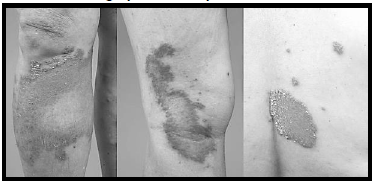

Paciente do sexo feminino, de 56 anos, procedente de Cuiabá, refere aparecimento de lesões isoladas em tronco e membros há 1 ano. Refere que há 3 meses houve crescimento progressivo das lesões, com acentuação do eritema. Nega prurido e episódios de febre.

enunciado 540561-1

Quanto aos achados mais prováveis dos exames laboratoriais, assinale a alternativa correta.